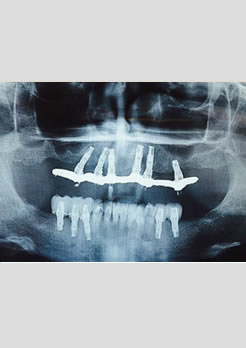

Instalação de 6 implantes na arcada superior com a técnica de carga imediata, com instalação da prótese em 48 horas

RX panorâmico dos implantes instalados